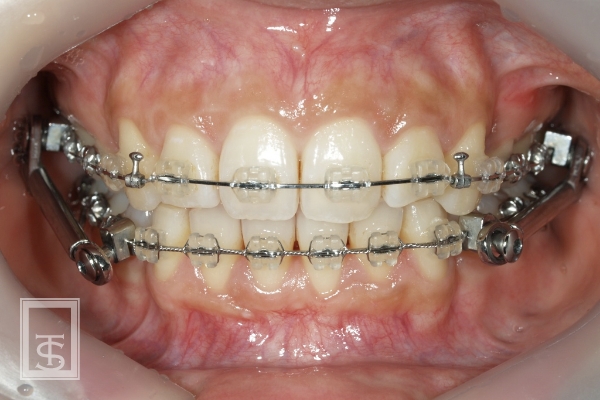

ハーブスト装置(Herbst appliance)

下顎骨成長促進、下顎骨前方誘導を行う装置となります。